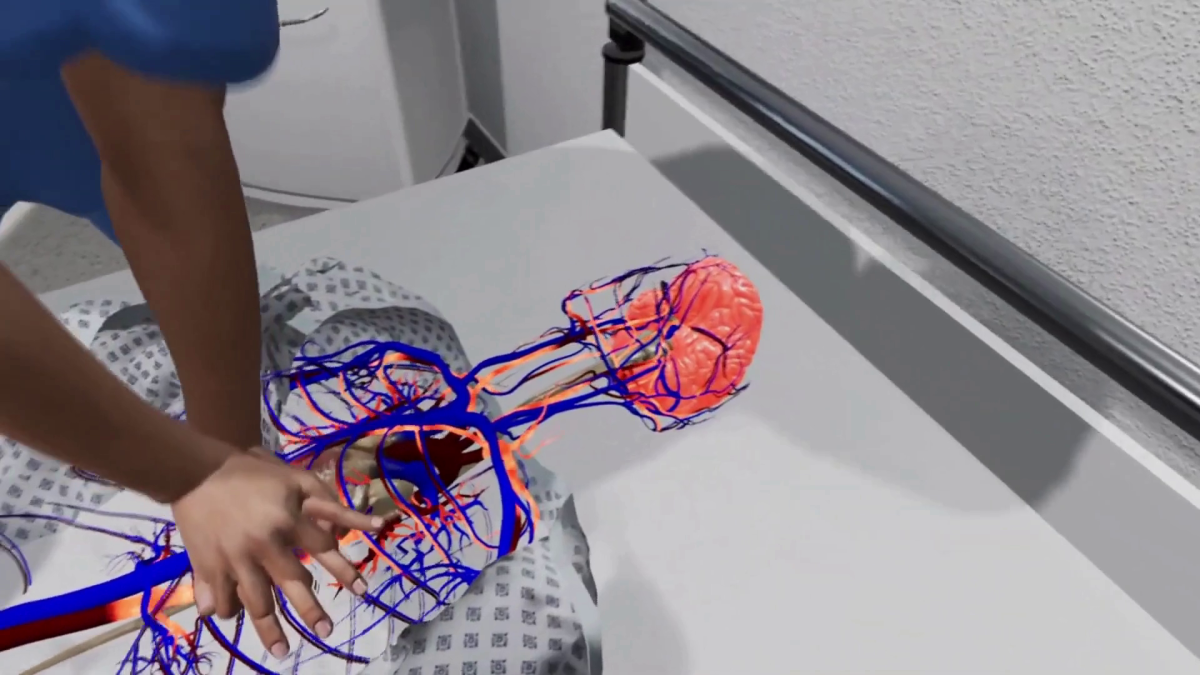

- 3D Dental Animation for procedures like cleaning, cavity filling, root canals, etc.

- Detailed oral health explainer videos that are engaging and easy to understand

I have extensive experience in dental visualization and animation, ensuring that every project is accurate, professional, and visually appealing. I use advanced software to deliver high-quality videos tailored to your specific needs.

Tagged : 3d dental animation, 3d medical animation, dental models for oral health explainer, surgical animation, tray whitening